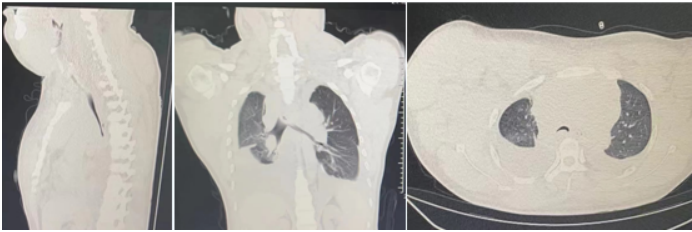

12月8日复查胸部CT,气管管径较前明显增宽(图10)。患者于12月14日出院,于当地定期复查。病例3:80岁,男性,发现颈部肿块5年,咳嗽气促1个月入院(2024年1月6日)。2019年1月14日曾于外院置入气管硅酮支架。术前(1月6日):HR 95次/min,R 22次/min,静息下SpO2 97%(FiO2 29%),活动后喘鸣。1月8日硬镜示:气管上段膜部肉芽样新生物致管腔混合性重度狭窄(外压为主),冷冻+直钳清除气管上段膜部新生物(质韧,活检困难),术后直钳上调硅酮支架至气管起始部,完全覆盖狭窄处(图11),术后气促明显改善。术后病理:鳞状上皮化生,伴轻度非典型增生。1月12日凌晨1:09突发气促加重,喘鸣明显,HR 140次/min,BP 200/102 mmHg,R 35次/min,SpO2 97%(FiO2 35%)。紧急联系介入和麻醉团队进行急诊介入治疗,无痛喉罩下正压通气,患者喘鸣消失。支气管镜示:声门下腔水肿,气管起始部见大块坏死物堵塞管腔,随呼吸呈活瓣样,管腔明显狭窄,予冷冻+钳夹清理,支架未移位(图12)。

1月12日复查CT:支架位置良好(图13)。予无创通气与高流量交替,拟T管置入。1月14日患者夜间出现刺激性咳嗽,1月15日复查气管镜(软镜)示:声门下腔水肿并坏死物致管腔中度狭窄(图14),冷冻清理坏死物后见硅酮支架下移10 mm,支架第二次移位;声门及声门下腔注入地塞米松5 mg。硅酮支架难题就是肉芽增生和移位,与家属充分沟通后同意T管置入。1月17日全麻硬镜:声门下腔及气管起始部黏膜水肿并坏死物致管腔轻度狭窄,取出硅酮支架,置入T管(图15)。1月19日和20日两次复查气管镜:T管在位,管腔上缘少许坏死物(图16)。病例4:85岁,女性,反复气促2年,外院住院考虑气管外压性狭窄,支架置入失败,心跳骤停,困难插管后3月7日转入我科。入科:气管插管,HR 96次/min,BP 107/86 mmHg,R 24次/min,SpO2 98%(FiO2 100%)。腹膨隆明显。急查胸腹CT示腹腔、纵隔、胸壁及颈部多发积气(图17)。予腹腔穿刺排气。3月11日复查CT示积气明显减少(图18)。3月12日行全院大会诊,考虑结节性甲状腺肿可能,可考虑外科手术。下一步治疗面临难题:继续插管?还是支架置入后手术?与家属充分沟通后,家属拒绝再次支架置入,故继续插管并于3月15日于耳鼻喉科行甲状腺全切术+气管悬吊重建术。术后第3天(3月18日)拔除气管导管,3月28日顺利出院(图19)。因此,并非所有良性气道狭窄都需要介入治疗,解除原发病因最重要。